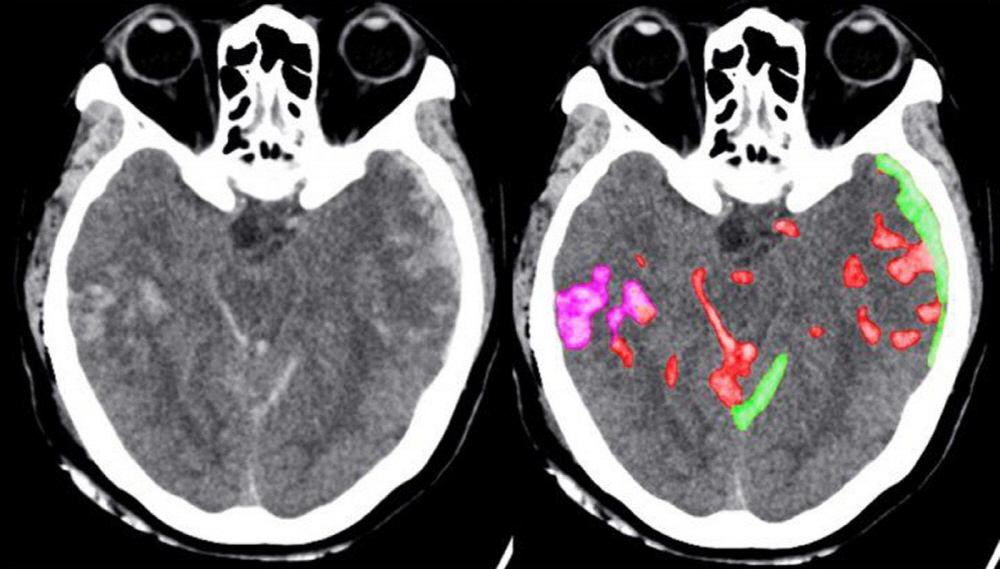

AI를 이용한 의료 영상 분석 처리는 이미 암 발견 등에 도움이 된다고 보고되고 있다. 반면 뇌출혈은 출혈량이 적더라도 심각한 문제가 ...